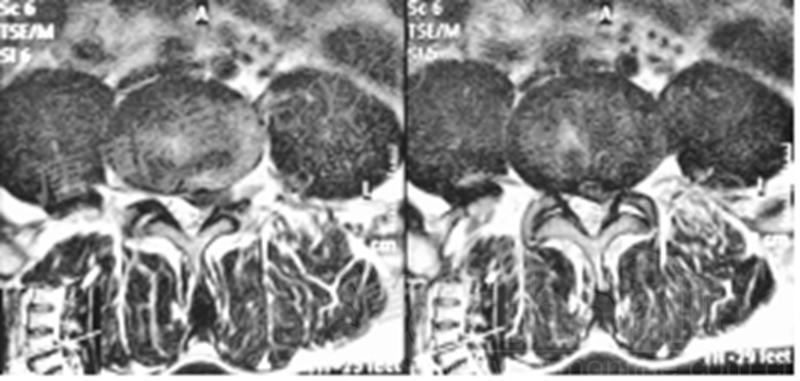

影像学检查:

诊断:腰椎间盘突出症术后复发

手术方案:显微镜辅助MI-TLIF腰椎翻修术

术中视频:http://api.orthonline.com.cn/attach/Case2.mp4(术中发现因前三次侧路及后路内镜手术的操作,术区大量瘢痕组织增生、与神经粘连严重;此外,摘除头侧游离髓核时连接有软骨终板脱落;在显微镜操作下,安全地将神经进行充分松解,压迫神经的游离髓核及软骨终板彻底清除。无手术并发症)